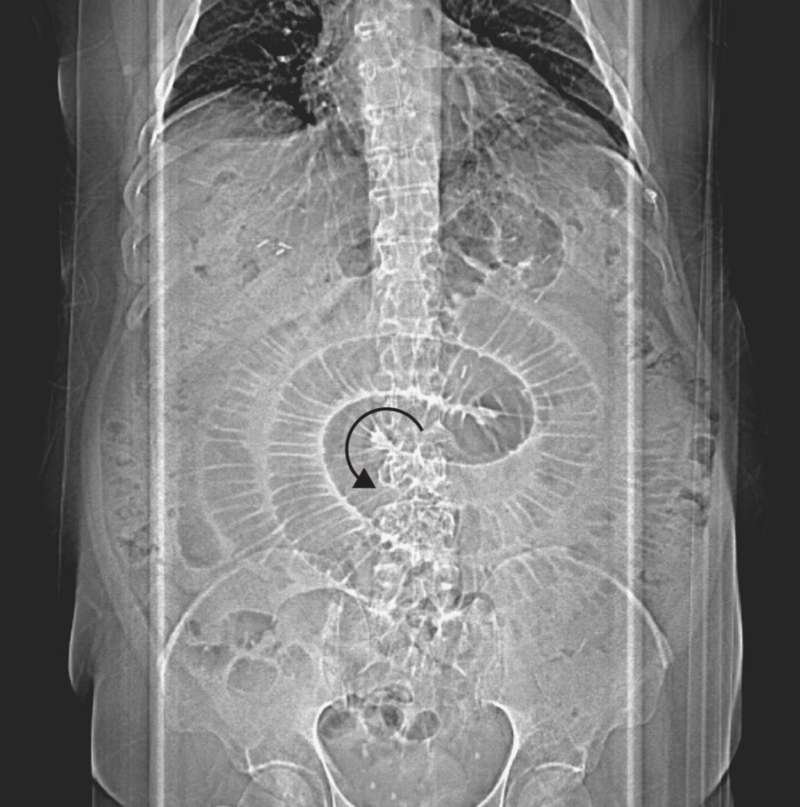

Patient with Abdominal Pain, Nausea, and Bilious Emesis Post category:Spot Diagnosis Post published:July 29, 2022 Share on Facebook Share on X (Twitter) Share on Pinterest Share on Email Share on Reddit X-ray of a Patient with Abdominal Pain, Nausea, and Bilious Emesis A 56-year-old man with a history of Roux-en-Y gastric bypass presented with abdominal pain, nausea, and bilious emesis. What is the diagnosis? CLICK FOR FULL CASE AND ANSWER Share on Facebook Share on X (Twitter) Share on Pinterest Share on Email Share on Reddit Read more articles Previous PostErythematous, Scaly and Hyperkeratotic Lesions Next PostPruritic, Umbilicated, Erythematous Vesicles with Erosion and Crusting You Might Also Like Patient with Progressively Worsening Abdominal Distention and Pain April 26, 2022 Patient with Intermittent Fevers and History of Recurrent UTI and Neurogenic Bladder January 28, 2022 Painless Erythematous Cutaneous Marks in a Fern-Leaf Pattern October 22, 2021